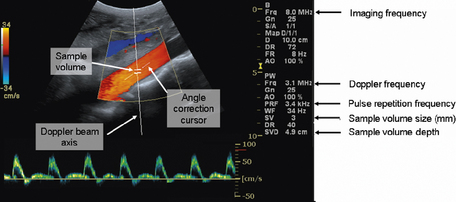

Spectral Doppler, also referred to as pulsed wave (PW) Doppler, is combined with B-mode and color flow imaging techniques and allows for the assessment and evaluation of the blood flow over a very small region known as the sample volume. This technique is known as range gating.

When spectral Doppler is initially instigated, a single Doppler beam axis is superimposed onto the B-mode and color flow image as illustrated in Figure 11.17. The size and position of the sample volume can be adjusted anywhere along the axis of the Doppler beam and this information is displayed on the monitor. The position of the sample volume determines where along the Doppler beam blood flow velocities are to be investigated. The size of the sample volume determines how much of the vessel is examined. For arterial examinations, the sample volume is positioned in the center of the vessel, and the size of the sample volume is set to be approximately one half to one third of the diameter of the vessel.

image

Fig. 11.17 Illustration of the on-screen components when spectral Doppler is activated. Highlighting the Doppler beam axis, the sample volume, and angle correction cursor. The size and position of the sample volume is always displayed on screen

The Doppler beam itself can be maneuvered over the B-mode image and follows the path of the B-mode imaging scan lines for a sector array transducer, as depicted in Figure 11.17. When linear array transducers are used, the Doppler beam can be steered, which enables the operator to achieve the necessary angle between the Doppler beam and blood vessel under investigation. An example of this is shown in Figure 11.18.

The angle correction cursor which is located at the center of the sample volume is used to estimate the angle of insonation between vessel and Doppler beam and should be adjusted to align with the direction of blood flow in the vessel to calculate absolute flow velocities from the detected Doppler shifted signals.

By angle correcting, the operator provides the ultrasound system with the actual value of θ in the Doppler equation. Once θ is known, the Doppler equation can be used to calculate actual blood flow velocities. Accurate and reliable spectral Doppler flow velocities are achieved for angles of θ, between the Doppler beam and the direction of blood flow, which are no greater than 60°.